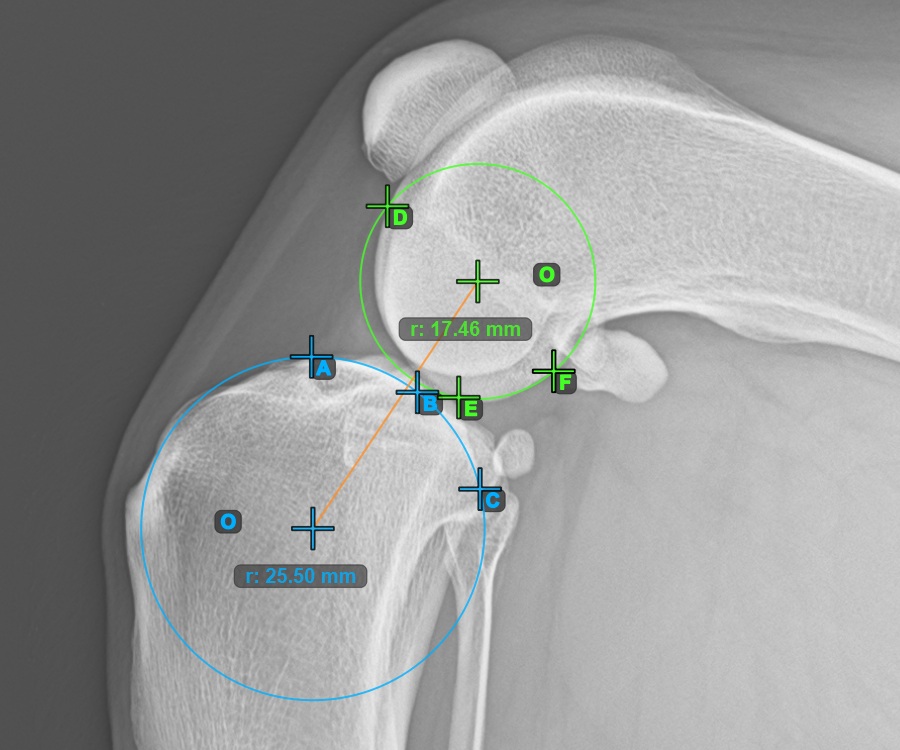

The image below represents a typical placement of the point on the common tangent between the two circles.

Start the TTA measurement procedure by marking the most cranial point of the Patella.

The image below depicts the usual placement of the most cranial point of the Patella.